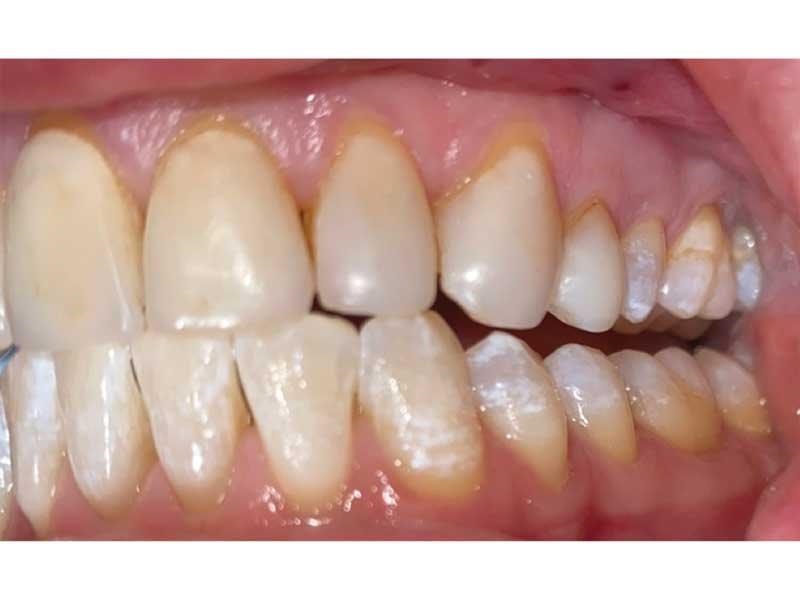

Meet Lorraine, who came into my office to “redo her bonding.” Lorraine had some upper anterior teeth done years ago with resin, which now was dull, stained and breaking down (Figs. 1–3). She had an amount of money in mind that she thought it would cost. She was very wrong.

Fig. 1

Fig. 2

Fig. 3